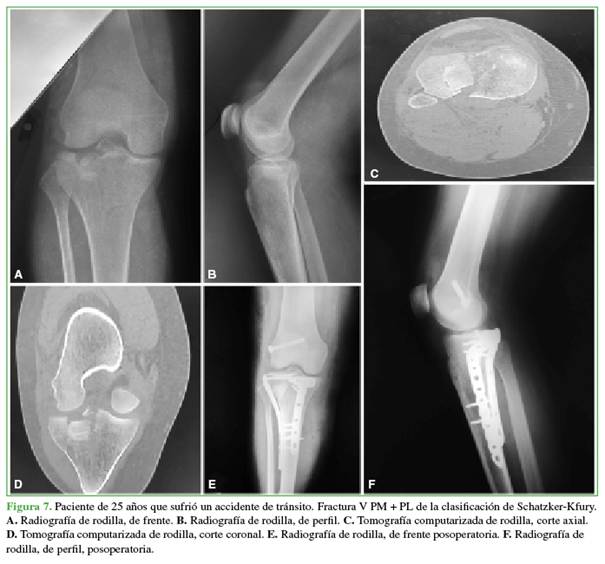

Se midieron el ancho condilar, el ángulo tibial proximal medial y la pendiente tibial, comparándolos con la rodilla contralateral, y arrojaron parámetros normales. Todos tenían un hundimiento <2 mm, excepto un paciente con un hundimiento de 3 mm. No hubo casos de seudoartrosis o desplazamiento del taco óseo de la osteotomía (Figuras 7 y 8).